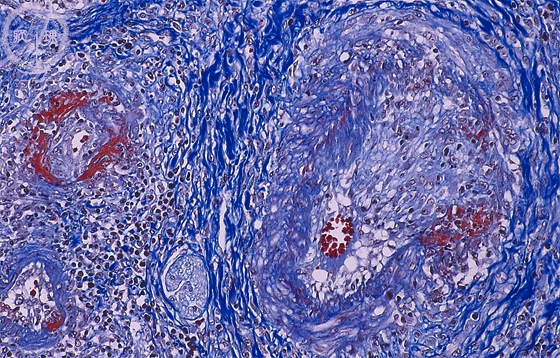

Microscopic image (Azan stain, high power view): Polyarteritis nodosa involving the liver. There is evidence of different phases of vasculitis.

Click the image to see the enlarged image.

• There is no guidance by arrows.